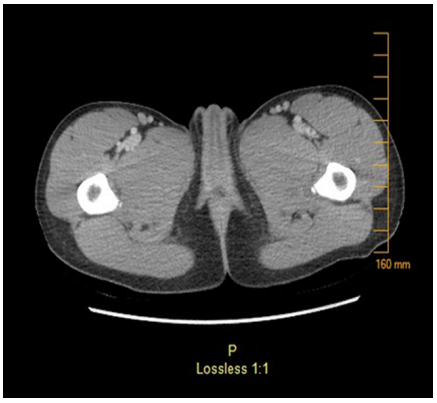

Physical examination reveals an anxious child, crying with pain. Her temperature is 38.7°C, heart rate is 109beats/min, blood pressure is 114/73 mm Hg, respiratory rate is 20 breaths/min, and oxygen saturation is 99% on room air. She has swelling and redness of clitoris, labia majora and labia minora with clear vaginal discharge observed on examination (Figure 1). There are bilateral ruptured vesicles on labia minora with dark discoloration of <1 cm on the right side. She also has moderate tenderness to palpation over the genital area, inner thighs, and bilateral enlarged inguinal lymph nodes. Her laboratory results are as follows: WBC count, 2.56×103/mcL (2.56×109/L) (52% neutrophils, 38% lymphocytes, 8% monocytes, 0.5% eosinophils); Hgb, 13.0 g/dL (133 g/L); Hct, 39% (0.39); and platelet count, 189×103/mcL (189×109/L). Her serum electrolytes and liver enzymes are normal. Her urinalysis obtained through a catheter shows clear yellow urine with negative leukocyte esterase and nitrite tests, 0 WBC/high power field (hpf), and 0 red blood cell/hpf. Viral PCR from genital lesions is negative for HSV 1 and 2. Serology for Cytomegalovirus (CMV) is negative for IgM and IgG. Epstein - Barr virus (EBV) mononuclear spot test and serology panel are negative for acute or past infection. ANA Screen Multiplex, ANCA Screen, and HCG Beta Subunit are all negative. A CT scan of the pelvis with contrast shows swelling and protrusion of the clitoral hood without evidence of any collection (Figure 2). A blood test reveals the diagnosis.

Figure 2 CT scan of the pelvis with contrast shows swelling and protrusion of the clitoral hood without evidence of any collection.